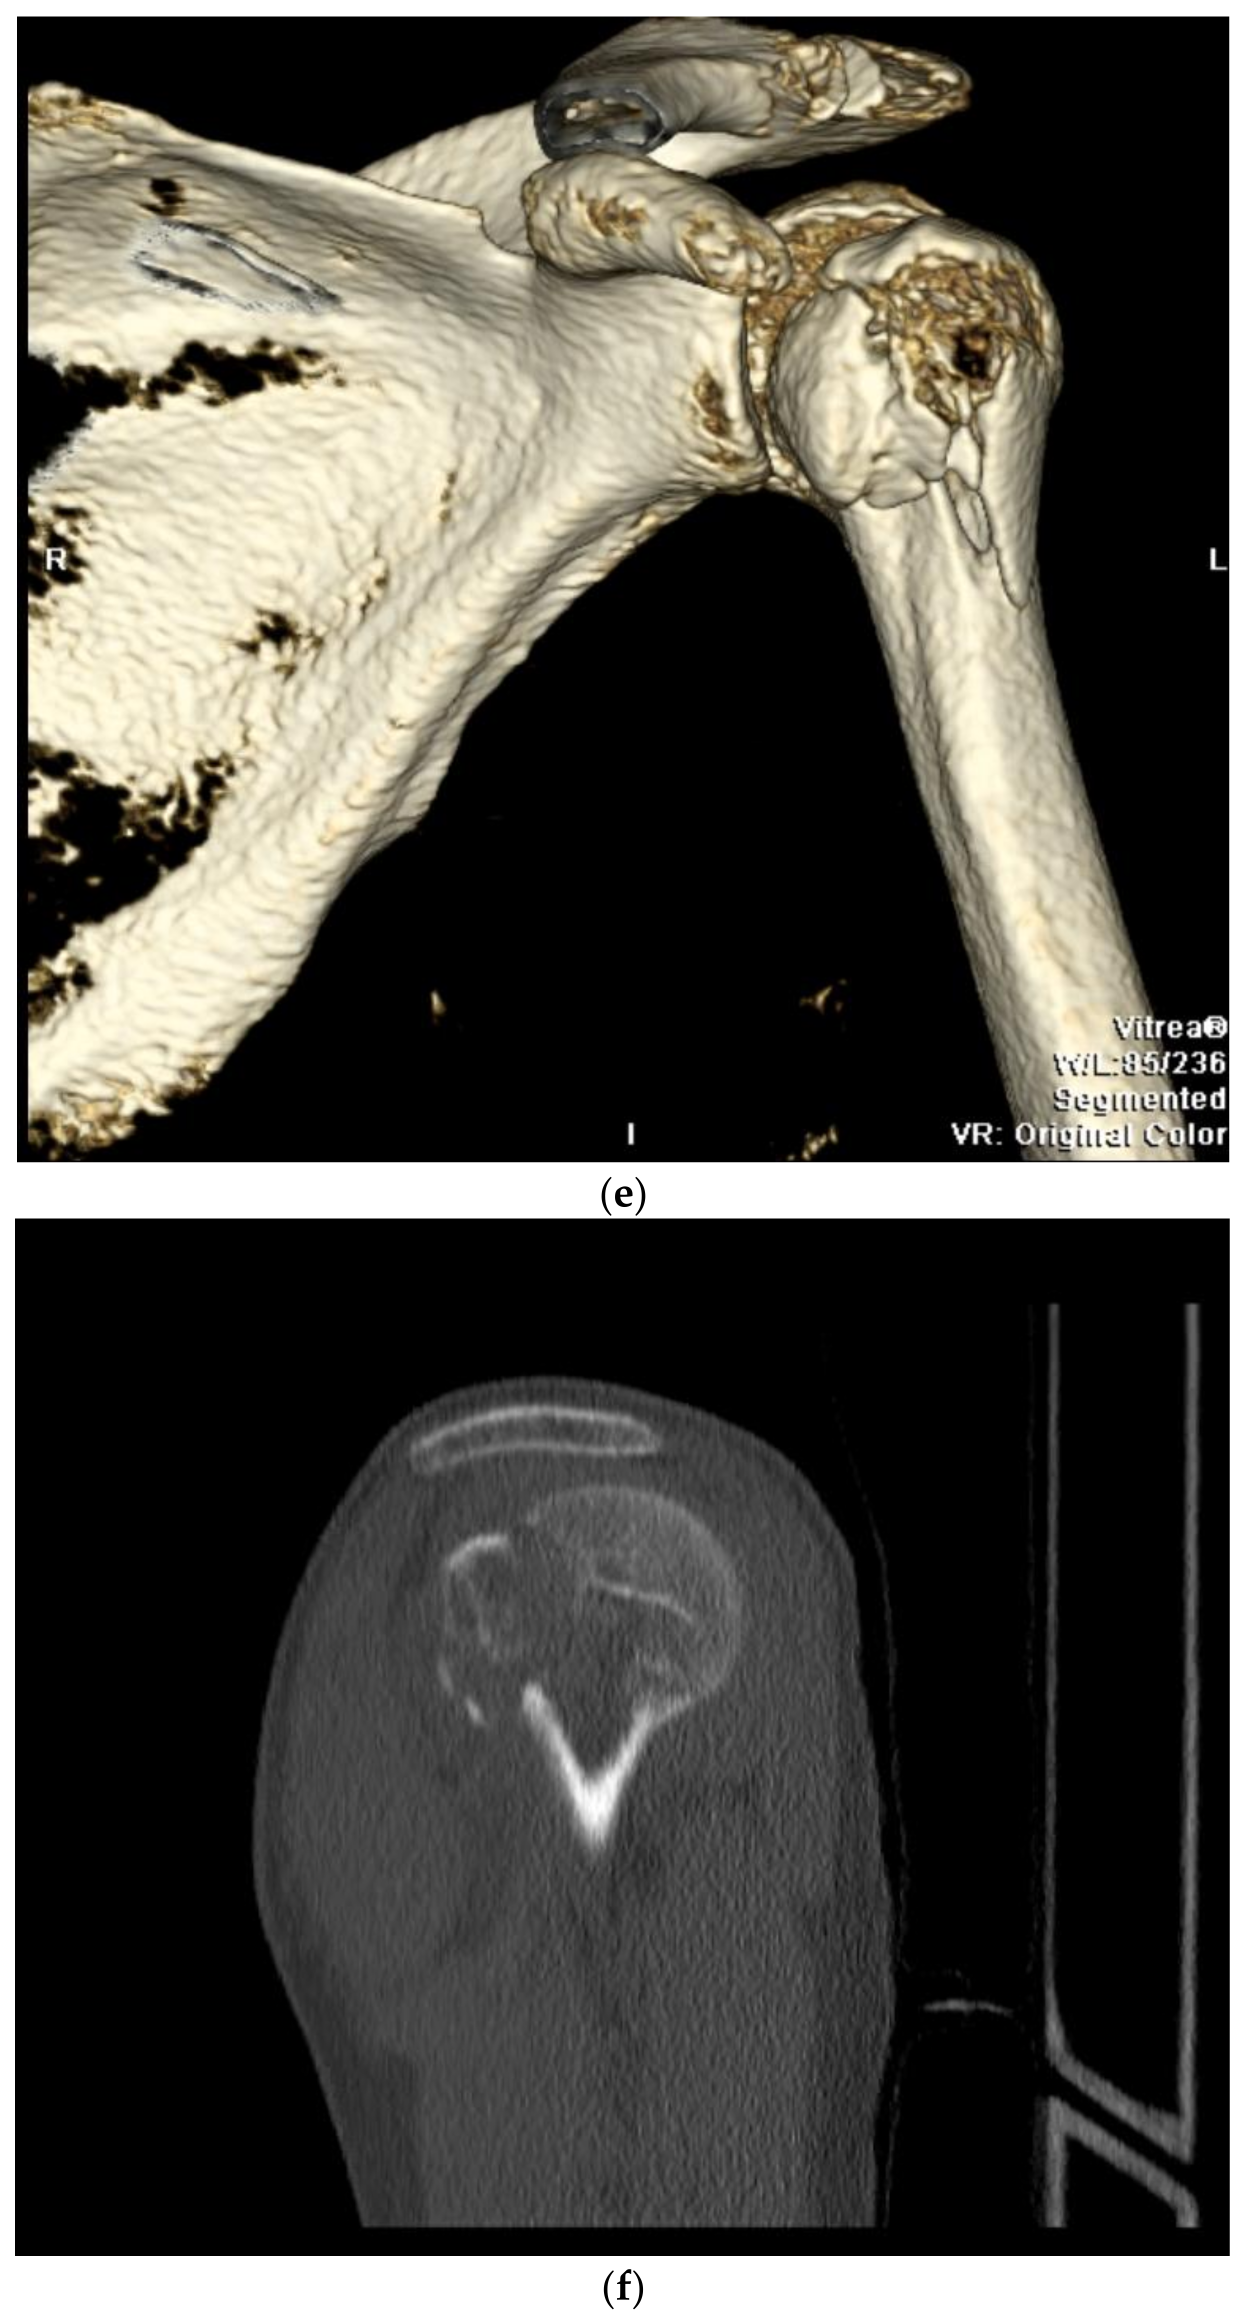

9. Open Reduction and Internal Fixation

10. Surgical Approach

10.2. Surgical Technique

10.3. Fracture Reduction

10.4. Fracture Fixation